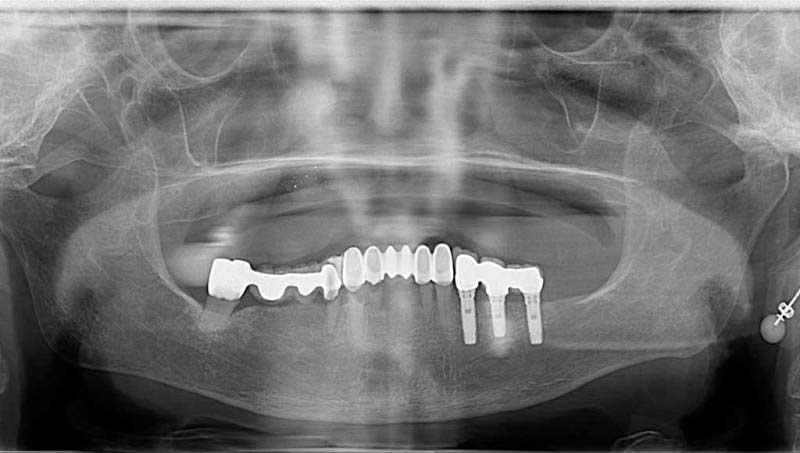

案例4